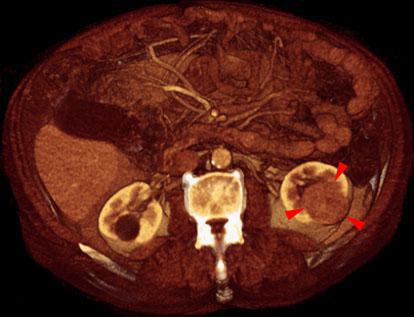

Hipernefroma 1

VR seccional. Visión axial caudal. Estudio contrastado en fase venosa que muestra en el riñón izquierdo una tumoración sólida (puntas de flecha), con realce del contraste, extendiéndose desde la cortical al seno renal